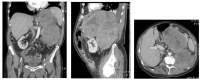

Murine Double Minute Clone 2, located at 12q15, is an oncogene that codes for an oncoprotein of which the association with p53 was discovered 30 years ago. The most important function of MDM2 is to control p53 activity; it is in fact the best documented negative regulator of p53. Mutations of the tumor suppressor gene p53 represent the most frequent genetic change in human cancers. By overexpressing MDM2, cancer cells have another means to block p53. The sarcomas in which MDM2 amplification is a hallmark are well-differentiated liposarcoma/atypical lipomatous tumor, dedifferentiated liposarcoma, intimal sarcoma, and low-grade osteosarcoma. The purpose of this review is to summarize the typical clinical, histopathological, immunohistochemical, and genetic features of these tumors.